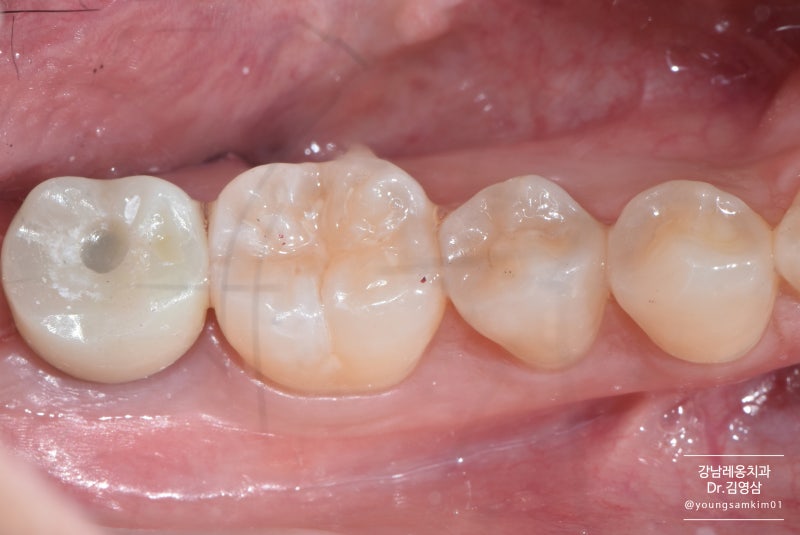

왼쪽의 사랑니와 오른쪽의 앞니. 사랑니 옆에 뿌리가 녹아 짧아지는 것을 보셨나요? 발치가 전혀 아깝지 않은 것이 현 상황입니다. 발치 후 엑스레이 사진입니다. 추출된 공간은 여전히 비어 있습니다. 염증이 없고 잇몸뼈의 상태가 양호하면 발치 당일 임플란트 식립이 가능하나, 이 경우 임플란트가 잘 고정되지 않아 실패할 확률이 높습니다. 사람마다 다르지만 뼈가 완전히 채워지는 데는 일반적으로 1~2개월 정도 걸립니다. 그 기간 동안 환자의 잇몸 상태가 좋지 않아 잇몸 치료를 시작하기로 했습니다. 환자가 항상 알아야 할 것은 치아를 오래 사용하기 위해서는 잇몸이 건강해야 한다는 것입니다. 노화가 진행됨에 따라 잇몸의 노화 과정이 서서히 사라집니다. 잇몸이 건강하면 치아를 지탱하는 잇몸뼈도 건강하기 때문에 잇몸이 좋지 않은 상태에서 치주치료를 지속하는 것이 좋습니다. 재생치료도 잇몸치료와 동시에 진행됩니다. 치아는 송곳니와 어금니 사이에 틈이 있기 때문에 “웃을 때 치아 사이 틈이 보여서 신경이 쓰인다”고 합니다. 수지가 벗겨지고 변색됩니다. 레진을 접착제로 붙이는 과정이기 때문에 칫솔질, 음식물 섭취 등 외부 자극에 의해 색이 진해지거나 사라질 수 있습니다. 다만, 치아가 빠지더라도 발치하지 않고 재수술이 가능하나, 레진치료 후 재수술 비용이 발생하게 됩니다. 공간이 자연스럽게 채워지나요? 위에서 언급한 것처럼 변색과 벗겨짐이 걱정된다면 교정이나 보철로 치료하는 것이 가장 좋다. 치아 사이가 벌어져 고민이시라면 치과에 내원하셔서 전문의와 상담을 받으시는 것이 좋습니다. 레진 전후 비교는 이제 2개월이 되었습니다. 잇몸뼈가 꽉 차 있는지 엑스레이를 찍었습니다. 2개월 전과 비교하면 다행히 뼈가 많이 자랐다. 이제 임플란트 식립이 가능해 당일 식립이 가능합니다. 치근에 해당하는 임플란트 픽스쳐만 식립합니다. 정확한 각도, 깊이 및 위치에 앵커를 설치하는 것이 중요합니다. . 누가 그렇게 좋아. . ^^ 잇몸뼈 상태가 좋지 않은 환자분들은 특히 힘듭니다. 이렇게 되기까지 약 2개월을 기다린 끝에 임플란트 헤드를 들어올리기로 결정했습니다. 2개월 후 치은골이 임플란트와 잘 맞는 것을 확인하고 최종 수복을 하였다. 방금 식립했을 때와 비교하여 X-ray 촬영 결과 주변 치은골이 잘 부착되고 단단해졌습니다. 첨부된 사진은 이식된 크라운의 사진입니다. 크라운 모양도 잘 되어있어요^^ 그리고 가운데 동그란 구멍도 똑같이 보이시죠? 이 구멍에는 임플란트의 뿌리와 헤드를 연결하는 작은 나사가 임플란트에 삽입됩니다. 임플란트 문제로 인해 보철물이 흔들리는 경우 이 구멍을 사용하여 임플란트를 조이는 나사를 조이거나 교체합니다. 임플란트 전보다 오른쪽 치아를 사용할 수 있어 오른쪽에서 편안하게 식사를 할 수 있어 마음이 편하다고 한다. 또한 환자가 몸이 좋지 않은 경우 염증이 이미 증가한 경우가 많습니다. 궁금하신 사항이 있으시면 언제든지 강남리온치과의원으로 연락주시기 바랍니다. 오늘도 좋은 하루 보내시길 바랍니다.서울시 서초구 강남대로 415 대동빌딩 4층 강남리온치과의원